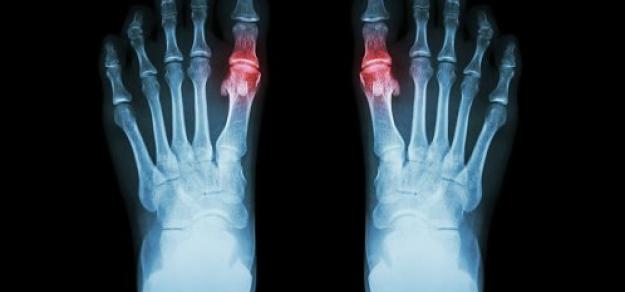

En estos datos basados ​​en la población, ni el inicio de alopurinol, ni el logro del nivel de objetivo de uricemia, ni el aumento de la dosis de alopurinol se asociaron con una mayor mortalidad en pacientes con gota y ERC concurrente. Annals of Internal Medicine, 25 de enero de 2022.

Asociación de enfermedad renal crónica con el uso de alopurinol en el tratamiento de la gota

JAMA Intern Med, 8 de octubre de 2018. En este estudio de cohorte de base poblacional del Reino Unido , el uso de alopurinol en pacientes con gota no aumentó el riesgo de disminución de la función renal, y se asoció significativamente con un riesgo 13% menor a dosis de 300 mg o más por día. Lo que significa que el alopurinol no parece estar asociado con una disminución de la función renal, y los médicos deben considerar otros contribuyentes potenciales cuando se enfrentan a una disminución de la función renal en pacientes con gota.